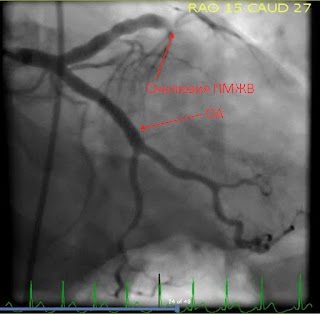

Первый взгляд на левую главную КА и ее ветви. Что Вы видите?

Нормальная левая главная КА. Огибающая - без препятствий для кровотока, ПМЖВ в верхней части изображения практически полностью закрыта (стрелка).

Интервенционалист описал это следующим образом: «99% тромботический стеноз» с «кровотоком TIMI-1», однако вы можете сами убедиться, что дистальнее окклюзии - кровотока НЕТ. Это полная окклюзия, и для того, чтобы вызвать немедленное развитие трансмуральнного инфаркта совсем не требуется 100% прекращение кровотока в виде TIMI-0.

В этой проекции ПМЖВ на изображении теперь находится ниже ОА. Для подготовки к вмешательству проводник расположен проксимальнее окклюзии.

После раскрытия стента начинается реперфузия дистальных сегментов ПМЖВ.

По заключению интервенционалиста был восстановлен кровоток TIMI-3.

После вмешательства восстановился кровоток TIMI-3 и боль у пациента стихла.